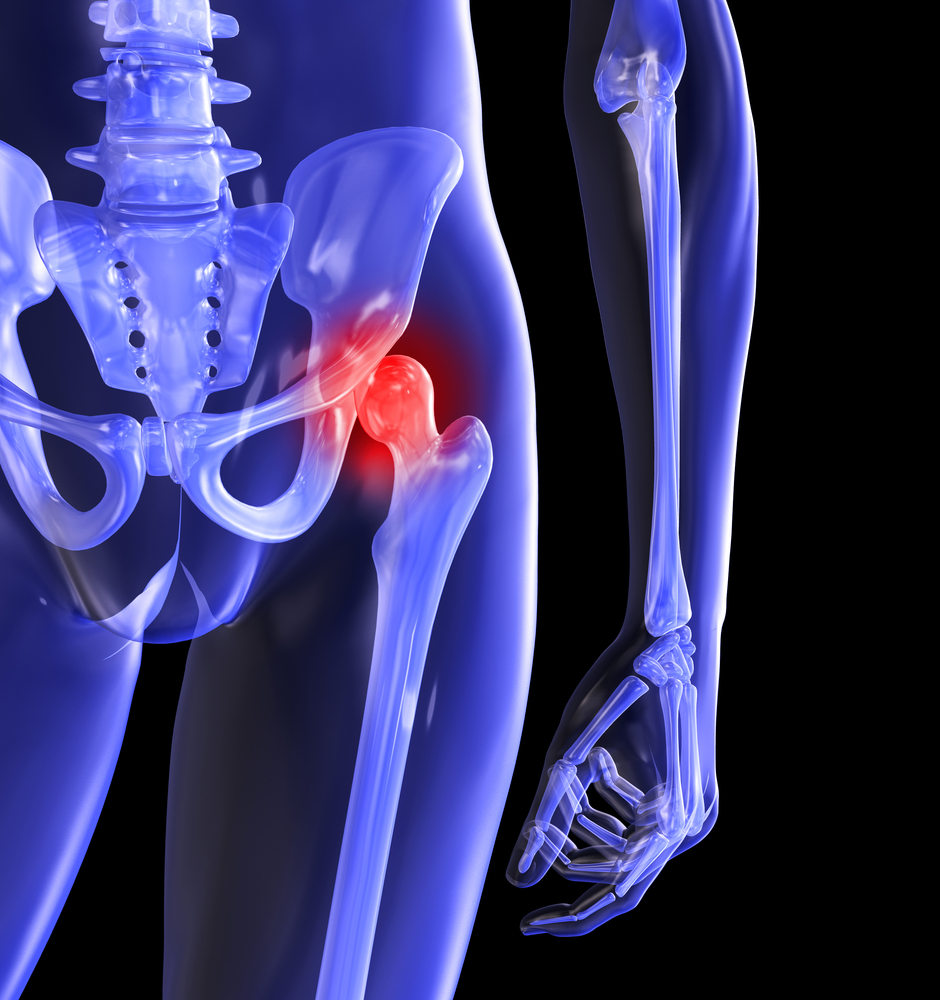

Why Rothman?

The joint replacement team at Rothman Orthopaedic Institute performs more than 9,000 surgeries every year. Each member of the team is specially trained, has extensive experience and is skilled to perform total joint replacements. Every physician that is a part of this outstanding team of doctors has undergone extensive subspecialty training during his/her residency and fellowship. This team is at the cutting edge of new research in the joint replacement field and Rothman physicians are actually responsible for training other orthopaedic surgeons through international lectures, webcasts, and surgical satellite simulcasts.